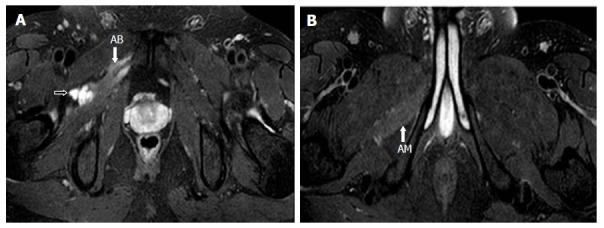

A retrospective analysis of the magnetic resonance (MR) images of a cohort of 245 patients presenting with nerve palsy involving different peripheral nerves was done. MR images were analyzed for the presence of a nerve lesion, and if found, it was further characterized as solid or cystic. The serial axial, coronal and sagittal MR images of the lesions diagnosed as INGC were studied for their pattern and the anatomical extent along the course of the affected nerve and its branches. Its relation to identifiable anatomical landmarks, intra-articular communication and presence of denervation changes in the muscles supplied by involved nerve was also studied.

A total of 45 cystic lesions in the intra or extraneural locations of the nerves were identified from the 245 MR scans done for patients presenting with nerve palsy. Out of these 45 cystic lesions, 13 were diagnosed to have INGC of a peripheral nerve on MRI. The other cystic lesions included extraneural ganglion cyst, paralabral cyst impinging upon the suprascapular nerve, cystic schwannoma and nerve abscesses related to Hansen's disease involving various peripheral nerves. Thirteen lesions of INGC were identified in 12 patients. Seven of these affected the common peroneal nerve with one patient having a bilateral involvement. Two lesions each were noted in the tibial and suprascapular nerves, and one each in the obturator and proximal sciatic nerve. An intra-articular connection along the articular branch was demonstrated in 12 out of 13 lesions. Varying stages of denervation atrophy of the supplied muscles of the affected nerves were seen in 7 cases. Out of these 13 lesions in 12 patients, 6 underwent surgery.